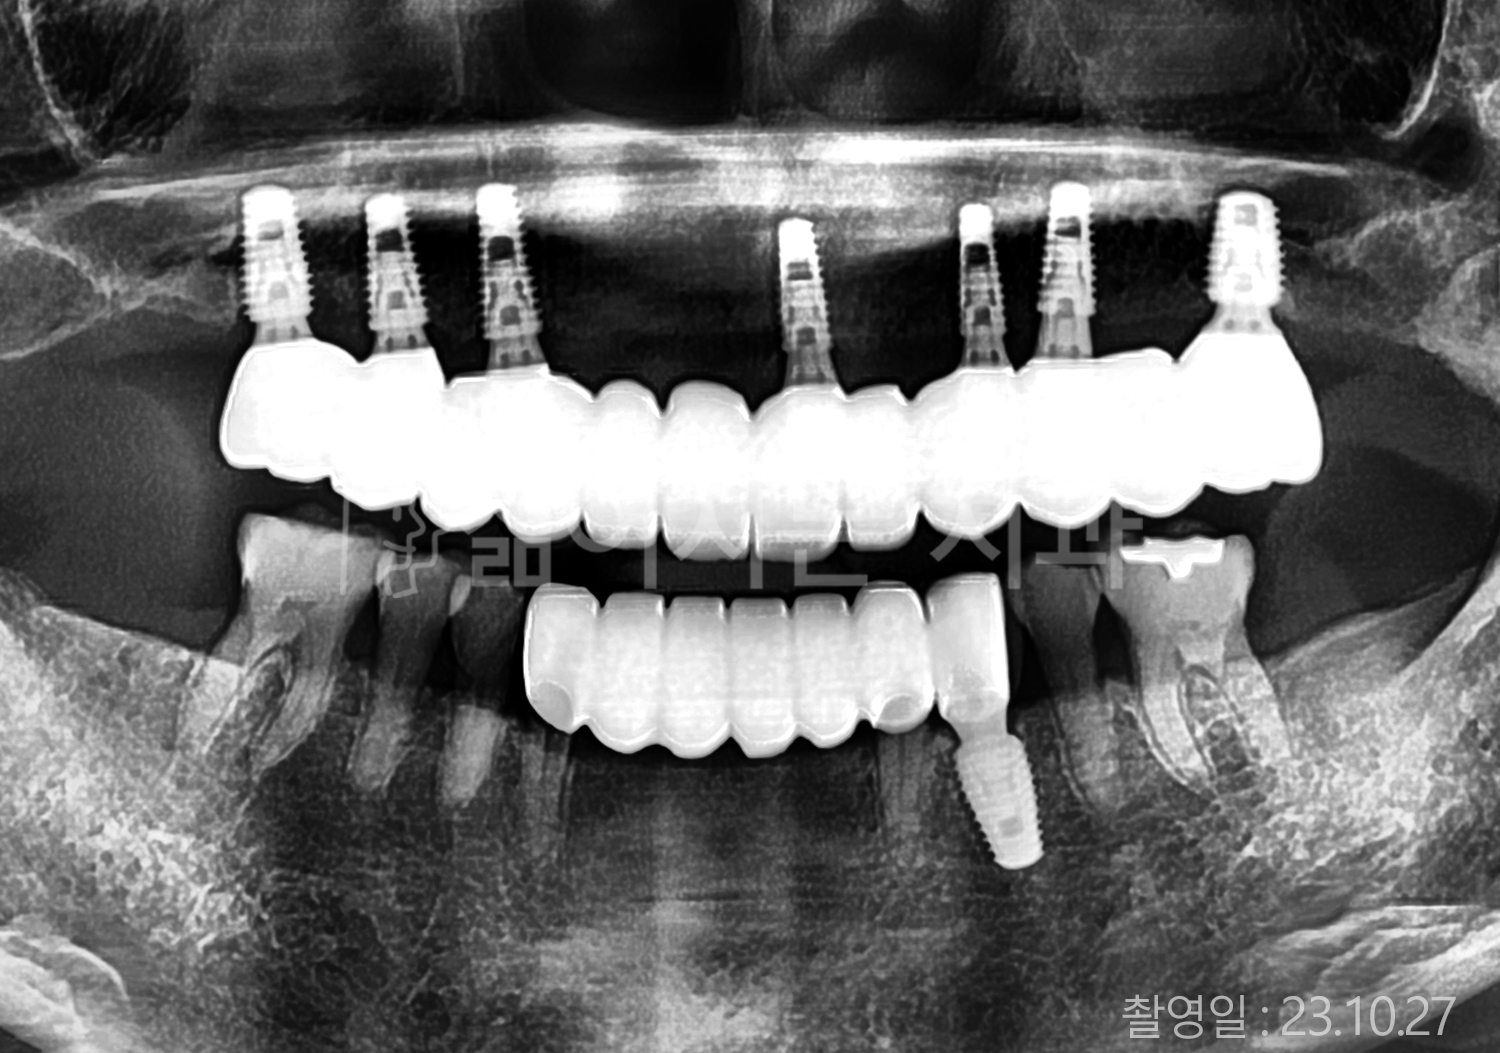

• 80대 전체치아 10개 이상 임플란트

• 60대 고혈압, 당뇨, 고지혈증 전체치아 10개 이상 임플란트

• 60대 전체치아 10개 이상 임플란트

• 60대 고혈압, 고지혈증 전체치아 10개 이상 임플란트

• 50대 고혈압, 당뇨, 고지혈증 전체치아 10개 이상 임플란트

• 70대 골다골증, 파킨스병 전체치아 10개 이상 임플란트

• 40대 전체치아 10개 이상 임플란트

• 60대 골다골증 전체치아 10개 이상 임플란트

• 40대 고혈압 전체치아 10개 이상 임플란트

• 50대 전체치아 10개 이상 임플란트

• 70대 전체치아 10개 이상 임플란트